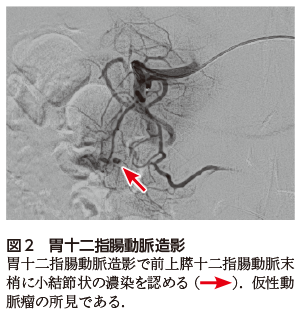

腹部CT(図1)にて十二指腸乳頭部仮性動脈瘤による胆道出血と診断され,緊急血管造影検査を施行した(図2).前上膵十二指腸動脈の仮性動脈瘤が明らかとなり金属コイルを用いた塞栓術が施行された.その後,再出血なく,貧血は改善し退院となった.

仮性動脈瘤の診断は造影CTに基づいて行われることが多い.非造影CTで消化管内腔あるいは消化管近傍の高濃度域は血腫を示唆し,造影CTの動脈相で点状や結節状の造影効果を示し,平衡相でも造影剤の形態が変化しない(図1).一方,血管外漏出像は動脈相から後期相にかけて造影剤の形態が拡大するものをいう3).責任血管は造影CTで同定できることもあるが,空間分解能,時間分解能に制限があり,難渋することもある.確定診断および治療には,診断と同時に治療(塞栓術)が可能な血管造影検査が選択されることが多い.

図1